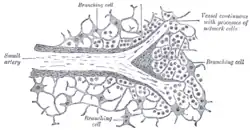

Section of the spleen, showing the termination of the small blood vessels. | |

The arterioles, supported by the minute trabeculae, traverse the pulp in all directions in bundles (penicilli) of straight vessels.

Their trabecular sheaths gradually undergo a transformation, become much thickened, and converted into adenoid tissue; the bundles of connective tissue becoming looser and their fibrils more delicate, and containing in their interstices an abundance of lymph corpuscles.

The altered coat of the arterioles, consisting of adenoid tissue, presents here and there thickenings of a spheroidal shape, the white pulp.

The arterioles end by opening freely into the splenic pulp; their walls become much attenuated, they lose their tubular character, and the endothelial cells become altered, presenting a branched appearance, and acquiring processes which are directly connected with the processes of the reticular cells of the pulp.

In this manner the vessels end, and the blood flowing through them finds its way into the interstices of the reticulated tissue of the splenic pulp.